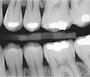

With a state-of-the-art digital radiography system, we can take your digital X-rays with significantly less radiation exposure than traditional X-ray imaging systems. This system also enables our patients to see their X-rays within seconds on their chairside monitor.